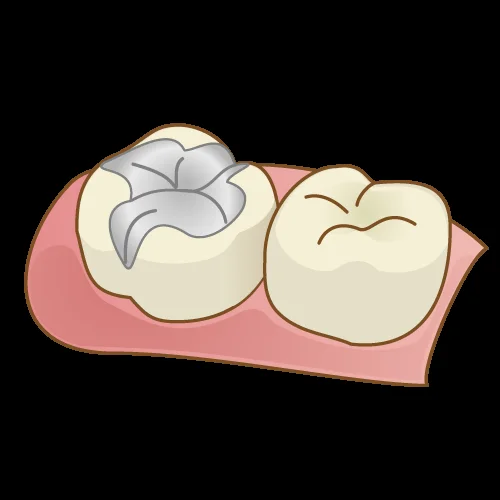

インレーとは、こういったやつですね。

ただ、インレーは保険でも自費でも日本中ありとあらゆる歯科医院にて多く行われている治療法ではありますが・・・実は非常に難しい治療の1つでもあります。